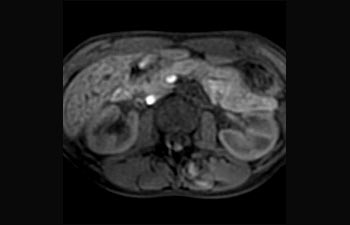

Liver and Pancreas